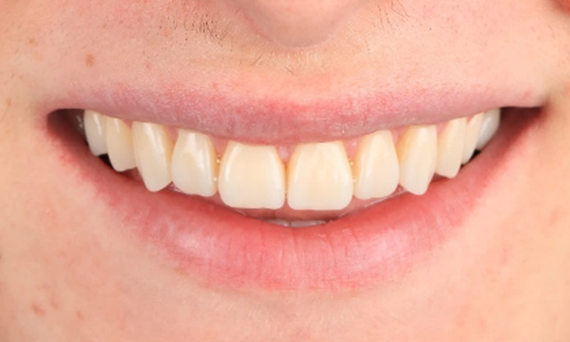

Before: Initial situation prior to orthodontic treatment.